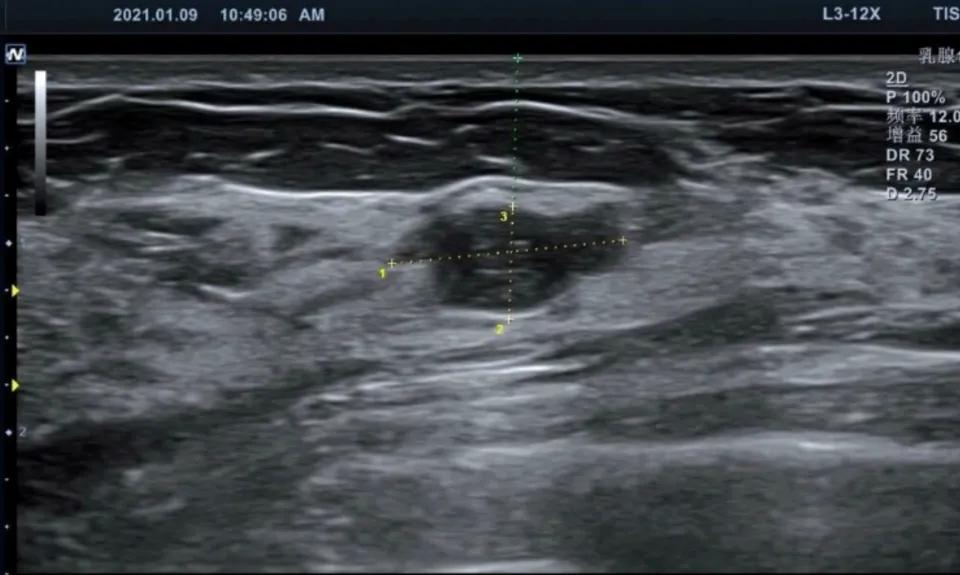

患者是一位35岁的女性朋友,拟备孕,为优生优育,在孕前检查的时候,做乳腺彩超:发现右乳房有1.5*1cm大小的结节,彩超结果提示右乳结节,BI-RADS 3类。平常除偶有来月经前乳房胀痛外,无其他症状,患者来就诊后一直纠结,要不要在备孕前治疗,手术。我接诊后:仔细阅读患者的彩超及图像,进一步做了乳腺钼靶检查,目的是看乳腺的结构以及有无恶性钙化,结果回示:未见异常钙化。初步诊断为:右乳结节,乳腺纤维瘤可能性大。

患者彩超图像